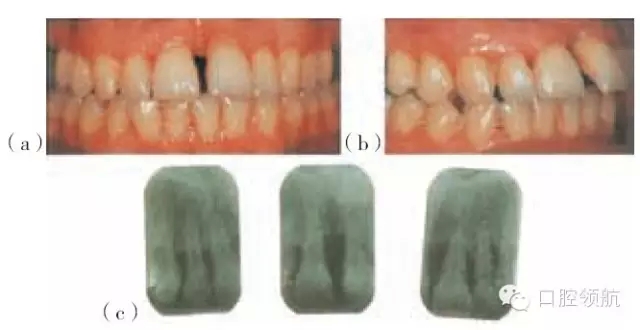

圖29.9 (a)慢性牙周病的成年女性患者,在牙周治療及正畸之前上中切牙移位。(b)治療后。(c)固定正畸保持器